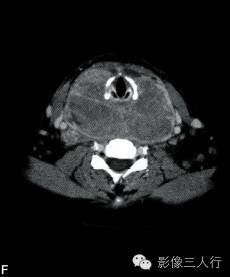

A~C.CT平扫横断面;D~F. CT增强横断面;G. HE×40

双侧甲状腺、颌下腺及咽淋巴环见多发结节融合状软组织影,边界不清,可见包膜,病灶密度欠均匀,内可见线样分隔,未见明显坏死及钙化,双颈各区可见大小不等的淋巴结,边界欠清,密度较均匀(图A~C)。增强横断面(图D~F)扫描双侧甲状腺、颌下腺及咽淋巴环病灶包膜及分隔可见明显强化,双颈淋巴结可见较明显强化。